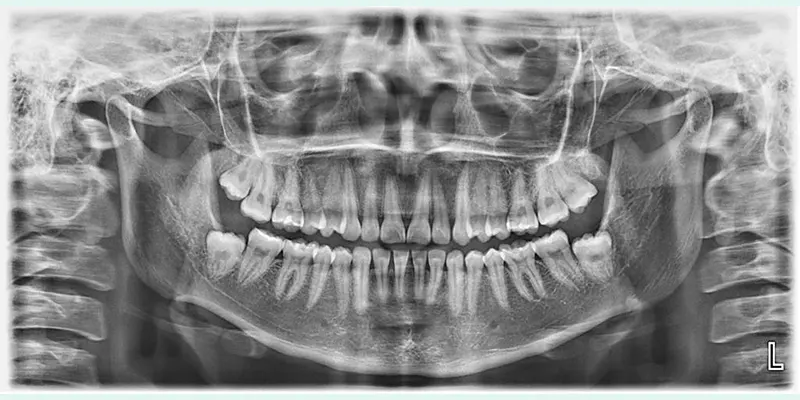

Es una categoría de servicios que utilizamos para obtener imágenes detalladas de tus dientes, mandíbula y estructuras dentales. Utilizamos equipos de vanguardia para garantizar la precisión y la seguridad durante el procedimiento.